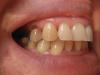

riana2 Опубликовано 22 августа, 2009 Автор Поделиться Опубликовано 22 августа, 2009 Мое партфолио готово, такая "красавица" получилась.Два крайних зуба подлежат удалению, а куда остальные денутся, хотелось бы сохранить. Здравствуйте!Если вам говорят,что имплантация вам не показана лишь по причине пародонтита,то жаль,жаль ваших докторов,искренне!Только они(импланты!) спасут вас от сЪемного протеза.Конечно не сразу,с предварительной подготовкой кости челюсти!И это нормальная практика.А бюгель опираться будет на верхний 4-й зуб?Да,запомните-Бюгель-бомба замедленного действия! Пожалуйста объясните подробнее какая предварительная подготовка требуется, какие импланты надо использовать в моем случае, что такое бюгель и куда лучше обращаться в Санкт-Петербурге. Ссылка на комментарий

Чиффа Опубликовано 22 августа, 2009 Поделиться Опубликовано 22 августа, 2009 фото в прикусе, желательно еще справа, слева и в анфас.половину вспышки прикройте пальцем и постарайтесь поточнее фокусироваться.Мое партфолио готово, такая "красавица" получилась.думаю, докторам нужны фотографии сомкнутых зубов справа, слева и по центру.... но лицо красивое! Ссылка на комментарий

riana2 Опубликовано 23 августа, 2009 Автор Поделиться Опубликовано 23 августа, 2009 думаю, докторам нужны фотографии сомкнутых зубов справа, слева и по центру.... но лицо красивое! Спасибо. ФОТОГРАФИИ. 3 ШТУКА. Ссылка на комментарий